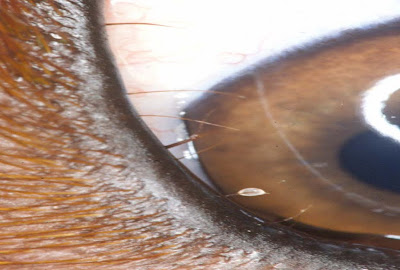

DISTICHIASI CANE 23 Maggio 2010 Dottor Prota Oftalmologia 60 SHARES Condividi su Facebook Tweetta adesso Follow us Share Share Share Share Share distichiasi cane, malattie palpebre cane, oculista cane, OCULISTA VETERINARIO NAPOLI ROMA BARI, Oftalmologia, Patologie occhio cane, peli ectopici cane Precedente Successivo